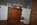

Seid Sonntag sind wir wieder glückliche Besitzer eines Ultraschallgerätes. Ein wunderbares leichtes und auch tragbares US. Durch liebe Menschen hatten wir glück dieses noch nicht so alte Ultraschallgerät zu bekommen. (War vor kurzem noch im Einsatz im KH Notaufnahme). Danke Pelin & Hanno